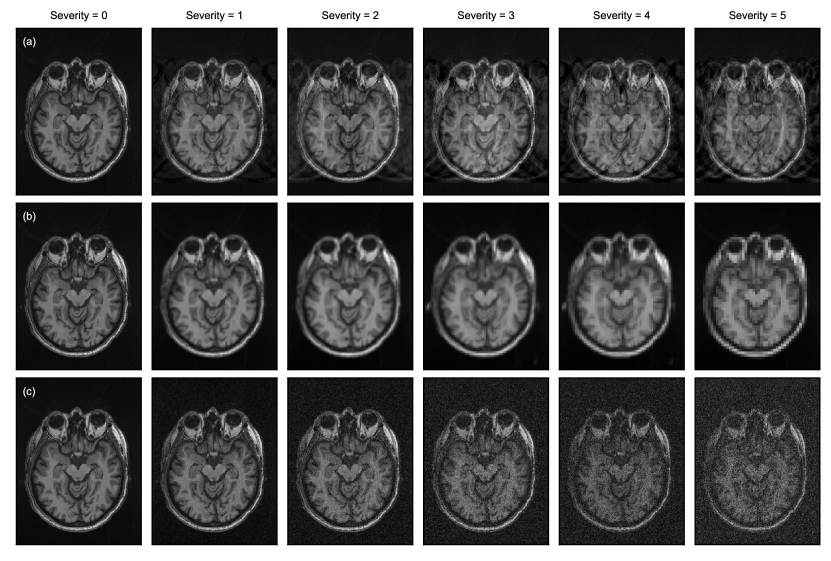

We simulate distribution shifts and corrupted data by applying transforms to images from a clean test set (Figure 1). We refer to the transformed test set as a benchmarking dataset. As shown in Figure 2, we selected 11 different transforms that cover distribution shifts across multiple categories discussed previously: (1) signal-to-noise ratio (SNR); (2) contrast and intensity non-uniformity; (3) image resolution and blurring; (4) spatial location of features (e.g., translations, rotations, deformations); (5) presence of motion artifacts. Ground truth segmentations were transformed accordingly and re-discretized for spatial transforms that alter the shape or orientation of the feature of interest (e.g., affine, elastic deformation, downsampling). Transforms were sourced from the Medical Open Network for AI (MONAI)222https://monai.io/ and TorchIO333https://torchio.readthedocs.io/ [Pérez-García et al., 2021] libraries, both part of the PyTorch Ecosystem [Paszke et al., 2019], or implemented where implementations were unavailable (e.g., for MRI [Rician] noise). See A for full descriptions of each transform and their formulations.

Following the approach of Hendrycks and Dietterich [2019], we defined five distinct severity levels for each transform (see Figure 3). Severity levels capture various magnitudes of distribution shifts, from mild to severe. Ideally, the chosen severity levels would span the range of distribution shifts seen in practice across imaging sites. However, there is a lack of quantitative studies investigating these ranges in the field, and it is not straightforward to translate observed variances into parametrically-modeled transforms. Thus, severity levels were chosen based on extensive visualization to fit in line with mild and extreme cases from the authors’ experience with multi-site studies, and corruptions observed in practice (e.g., due to poor quality, artifacts or patient movement). To properly model severity levels and corruptions, scans with artifacts were removed or corrected in our clean test set prior to transformation. These severity levels may need to be re-optimized or calibrated if applied to other applications/tasks where the dataset characteristics differ drastically from those used in this study. For transform parameterizations corresponding to each severity level, see Supplementary Table S1.